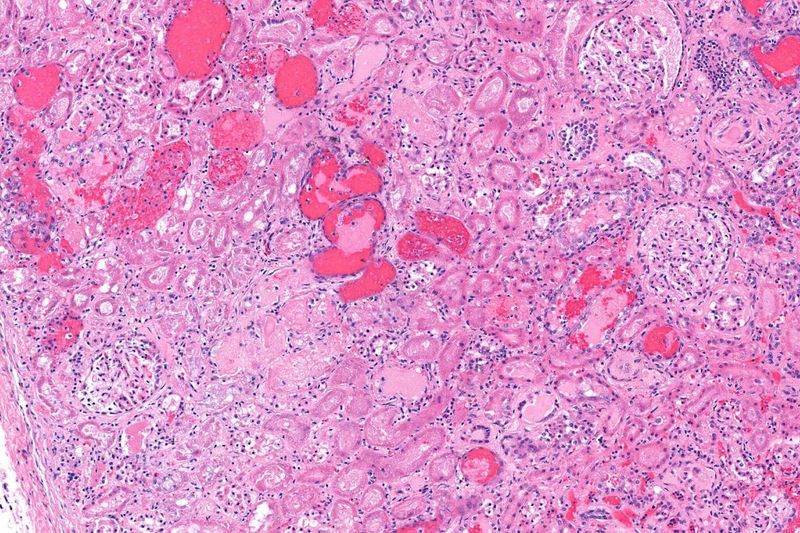

In HUS, the E. coli O157:H7 strain produces a poisonous substance called Shiga toxin, which can pass through the intestines into the bloodstream. The Shiga toxin then causes damage to red blood cells, platelets, and small blood vessels. The kidneys are the most targeted organ by Shiga toxin, but the brain, pancreas, liver, or heart may also be affected. As a result of this attack on the kidneys, HUS is the most common cause of sudden, short-term acute kidney failure in children.